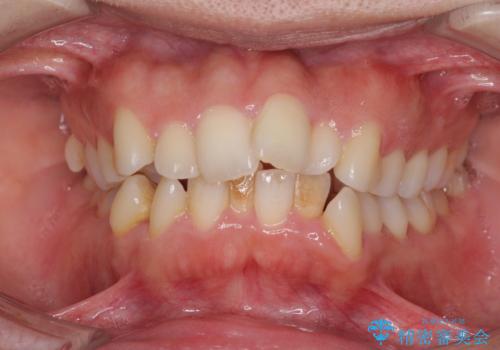

出っ歯を改善した後に真っ白な歯に 矯正歯科治療と審美歯科治療